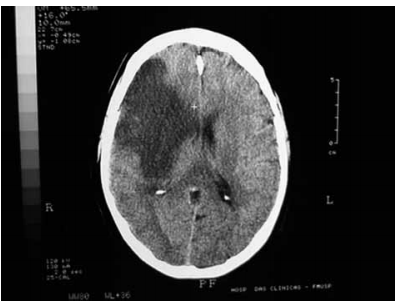

Paciente de 67 anos apresenta quadro súbito de hemiparesia. A tomografia está ilustrada a seguir.

Atualmente, há recomendação para realização de trombólise quando a janela entre o aparecimento dos sintomas e o início da trombólise é de